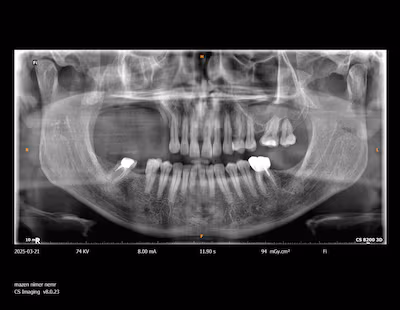

For this patient, the surgical team began by conducting a series of advanced scans to capture every detail of the jaw and facial structure. Using these scans, a digital model of the implant was created, ensuring that it would match the patient’s natural jawline. The 3D printer then produced the implant using durable, biocompatible materials, creating a perfect replica of the missing or damaged parts of the jaw.